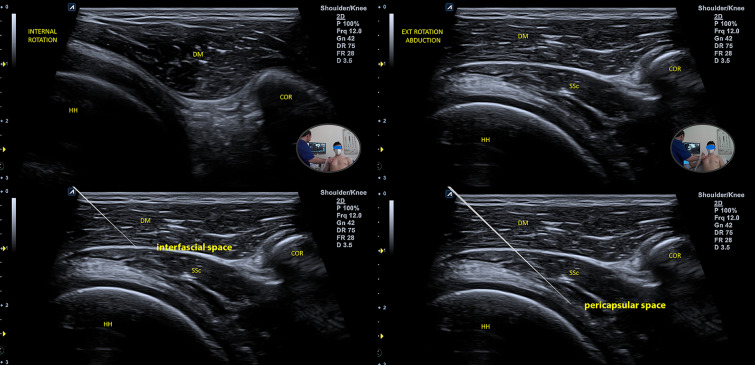

Description of the Procedures

For the SHAC block, with the patient in a beach-chair position and with the arm in extension, the subscapularis muscle is stretched posteriorly and becomes easily visible in the area below the deltoid fascia. With external rotation and abduction, the coracobrachialis and the biceps brachii muscles are displaced, allowing the visualization of the interfascial space between the deep lamina of the deltoid muscle fascia and the superficial lamina of the subscapularis fascia. The myotendinous nature of the lateral insertion of the subscapularis muscle produces a mixed echogenicity, with a characteristic dotted aspect that facilitates its localization in the US below the deltoid fascia (Fig. 1). Once the injection into the fascial space is achieved, we can proceed towards the glenohumeral pericapsular space by crossing the subscapularis muscle with the needle. By injecting the pericapsular space, we reach the terminal articular branches indistinctly from their origin. Furthermore, through the Weitbrecht foramen, a natural capsular foramen between the upper and middle glenohumeral ligaments, we also reach the intra-articular space (Fig. 2).

Fig. 2.

SHAC block procedure. HH humeral head, COR coracoid, SSc subscapularis, BB biceps brachii, CBM coracobrachialis, DM deltoid muscle